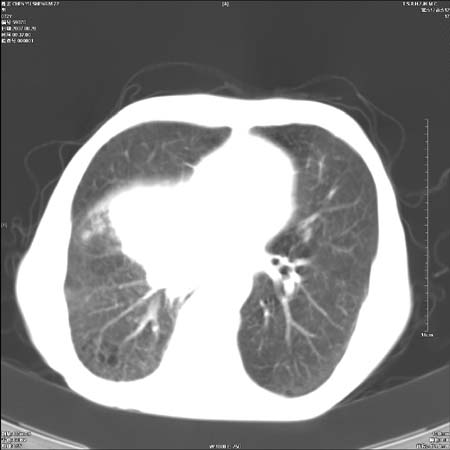

男性,72岁,既往肺结核,今复查。无前片对比。

纵隔窗

右侧中央型肺癌伴中叶不张可能性大,建议增强扫描.右上肺陈旧性肺结核.慢性支气管炎伴肺气肿.右侧少量胸腔积液.

右侧中央型肺癌伴中叶不张可能性大,建议纤支镜检查.右上肺陈旧性肺结核.肺气肿。

典型右肺中心型肺癌

右侧中央型肺癌伴肺不张可能性大,建议增强扫描.右上肺陈旧性肺结核.慢性支气管炎伴肺气肿.右侧少量胸腔积液.

右肺中心型肺癌

右侧中央型肺癌.上肺陈旧性肺结核.

1右侧中央型肺癌伴中叶不张2右侧少量胸腔积液3右上肺陈旧性肺结核

1.右肺中心性肺癌并右肺中叶综合征2。右侧胸腔少量积液3。右肺上叶结核球已钙化,4。慢支伴肺气肿

右侧中央型肺癌伴中叶不张可能性大,建议纤支镜检查.右上肺陈旧性肺结核.肺气肿。

右侧中央型肺癌伴中叶不张可能性大,建议增强扫描.右上肺陈旧性肺结核.慢性支气管炎伴肺气肿.右侧少量胸腔积液.

右侧中央型肺癌伴中叶不张

右肺中央型肺癌伴右肺中叶不张。

右上肺陈旧性肺结核。

支持右肺中心型肺癌并中叶不张,右上肺陈旧性肺结核钙化,右侧少量胸腔积液。

支持右侧中央型肺癌伴中叶不张可能性大,建议增强扫描.右上肺陈旧性肺结核.慢性支气管炎伴肺气肿.右侧少量胸腔积液.

支持 1右侧中心型肺癌伴中叶不张2右侧少量胸腔积液3右上肺陈旧性肺结核4双肺局限性肺气肿

1,右侧中央型肺癌.

2,右上肺陈旧性肺结核.

1.右侧中央型肺癌伴中叶不张,建议纤支镜检查.

2.右上肺陈旧性肺结核.

3.肺气肿。

4.右侧少量胸腔积液.

右侧中央型肺癌伴中叶不张并纵隔淋巴结增大,建议增强扫描.右上肺陈旧性肺结核.慢性支气管炎伴肺气肿.右侧少量胸腔积液。

右肺中心型肺癌并肺不张,陈旧性肺tb.慢支,肺气肿.

陈旧性肺结核.慢性支气管炎伴肺气肿,中央型肺癌伴中叶不张。

右侧中央型肺癌伴中叶不张可能性大;右上肺陈旧性肺结核.慢性支气管炎伴肺气肿

陈旧性结核是存在,但真正致命的却是右侧中心型肺癌。